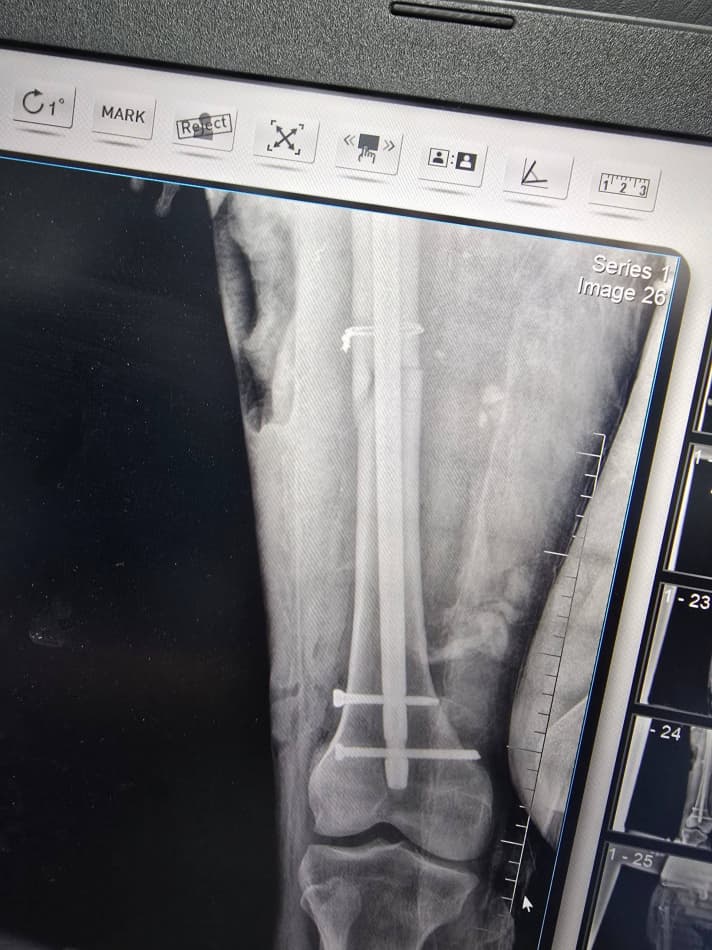

Маълум бўлишича, 1980 йилда туғилган бемор жорий йил 8 апрель куни уч ғилдиракли юк мотоциклида йўл-транспорт ҳодисасига учраб, турли даражадаги тан жароҳатларини олган. Тиббий кўрик натижасида беморга бош мия чайқалиши билан бирга чап оёғи сон суягининг ўрта учлигида очиқ синиш ташхиси қўйилди. Бундай ҳолатларда тезкор ва юқори малакали тиббий ёрдам ҳаётий аҳамият касб этади.

Шифокорлар томонидан беморнинг ҳолати чуқур ўрганилиб, замонавий усулда жарроҳлик амалиёти ўтказишга қарор қилинди. Хусусан, чап сон суягини тиклаш мақсадида каминвазив усулда блокланган интрамедулляр остеосинтез (БІОС) амалиёти бажарилди. Бу усул суяк ичига махсус металл имплант ўрнатиш орқали синишни ичкаридан мустаҳкамлашга хизмат қилади. Натижада операция кам жароҳат билан ўтади, қон йўқотиш камаяди ва беморнинг соғайиб, оёққа туриш жараёни тезлашади.